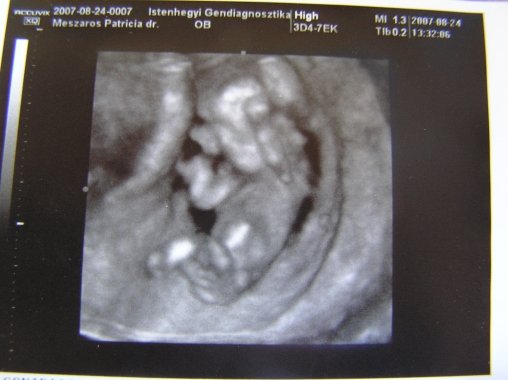

Gratula a kis túlélőhöz! Szerintem az a néhány napos eltérés a baba kora és mérete között egyáltalán nem számít. Emiatt ne aggódj! Sőt, ha belegondolsz, egy ilyen pici manókánál ha csak 1-2 mm-rel odébb teszi az x-et a doki, már mást mér.